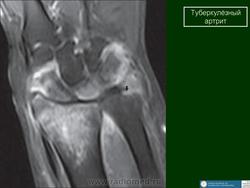

Туберкулез лучезапястного сустава

Эта локализация костно-суставного туберкулеза является одной из редких. Болеют как дети, обычно старше 3-х лет, так и взрослые. Первым клиническим симптомом является слабость в руке, небольшая припухлость мягких тканей. Вскоре появляются боли в области сустава, ограничение движений, атрофия мышц предплечья, образуются натечные абсцессы и свищи. Нередко поражение костей запястья бывает двусторонним или сочетается с поражением других крупных суставов (коленного, локтевого). Туберкулезный остит у детей чаще локализуется в головчатой и крючковидной кости (т. е. в тех костях, в которых раньше появляются ядра окостенения). Первичный очаг может располагаться также в костях проксимального ряда запястья или в лучевой кости, причем у детей нередко в метафизе. При локализации в метафизе лучевой кости первичный очаг переходит сначала на лучелоктевой сустав, а затем на лучезапястный. При рентгенологическом исследовании у детей до 10 лет обращает на себя внимание раннее появление ядер окостенения костей запястья, остеопороз, затем выявляются очаги деструкции костной ткани, которые содержат губчатые секвестры, а также сужение составных щелей между костями запястья и лучезапястного сустава. Постепенно остеопороз нарастает и может захватывать все кости кисти и предплечья. Контуры костей запястья могут быть нечеткими и местами вовсе не дифференцироваться. При локализации первичного очага в метафизе лучевой кости может отмечаться небольшое вздутие кости и периостальные наслоения, которые муфтообразно охватывают метафиз. Затихание процесса клинически характеризуется стиханием воспалительных изменений. При рентгенологическом исследовании появляется четкость контуров очагов деструкции костной ткани, склеротический ободок вокруг них. Остеопороз принимает репаративный характер — редкие костные балки представляются утолщенными и располагаются преимущественно по силовым линиям. Процесс заканчивается фиброзным или костным анкилозом с укорочением запястья. Постартритическая фаза характеризуется анатомо-функциональными изменениями, возможными рецидивами. При рецидивах нарастает остеопороз, контуры очагов деструкции и суставных поверхностей становятся нечеткими, появляются секвестры. Туберкулезное поражение лучезапястного сустава в ряде случаев приходится дифференцировать с неспецифическим остеомиелитом костей предплечья и фиброзной остеодисплазией. В ряде случаев может возникнуть необходимость в дифференциальной диагностике с ревматоидным полиартритом. Однако ревматоидный полиартрит встречается преимущественно у взрослых, характеризуется своеобразными клиническими проявлениями. При рентгенологическом исследовании выявляется преимущественно двустороннее поражение пястно-фаланговых, межзапястных, запястно-пястных, межфаланговых и лучезапястных суставов. На фоне остеопороза в околосуставных отделах выявляются множественные мелкие (2—3 мм) кистоподобные просветления округлой формы и краевые узуры с четкими контурами, окруженные ободком склероза. Секвестры отсутствуют, суставные щели сужены, однако контуры суставных поверхностей хотя и неровные, но четкие. Эти изменения часто ведут к подвывихам и анкилозам. При проведении дифференциальной диагностики необходимо помнить об асептическом некрозе луновидной кости запястья, который встречается у взрослых после однократной травмы или множественых микротравм. При рентгенологическом исследовании луновидная кость уплощена, уплотнена, фрагментирована. Суставные щели не изменены. Остеопороз отсутствует. Свищей и абсцессов не бывает.